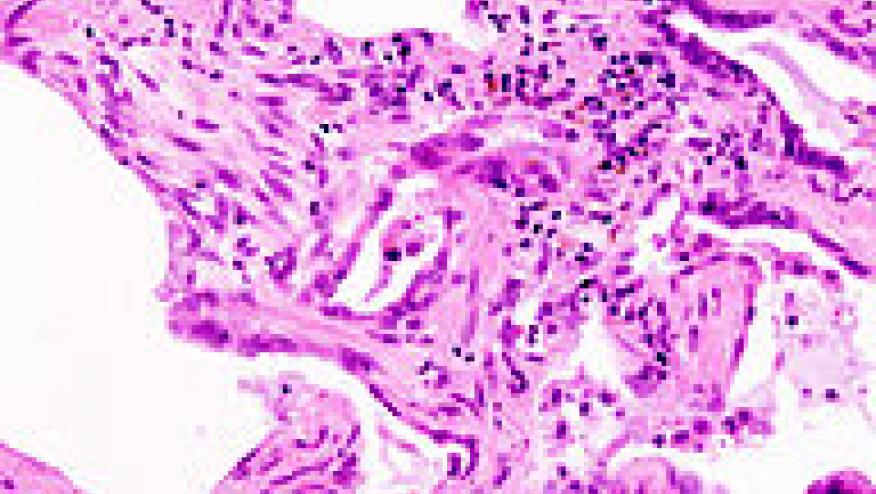

[Image: "Usual interstitial pneumonia (1)" by No machine-readable author provided. KGH assumed (based on copyright claims). - No machine-readable source provided. Own work assumed (based on copyright claims).. Licensed under CC BY-SA 3.0 via Commons - ]